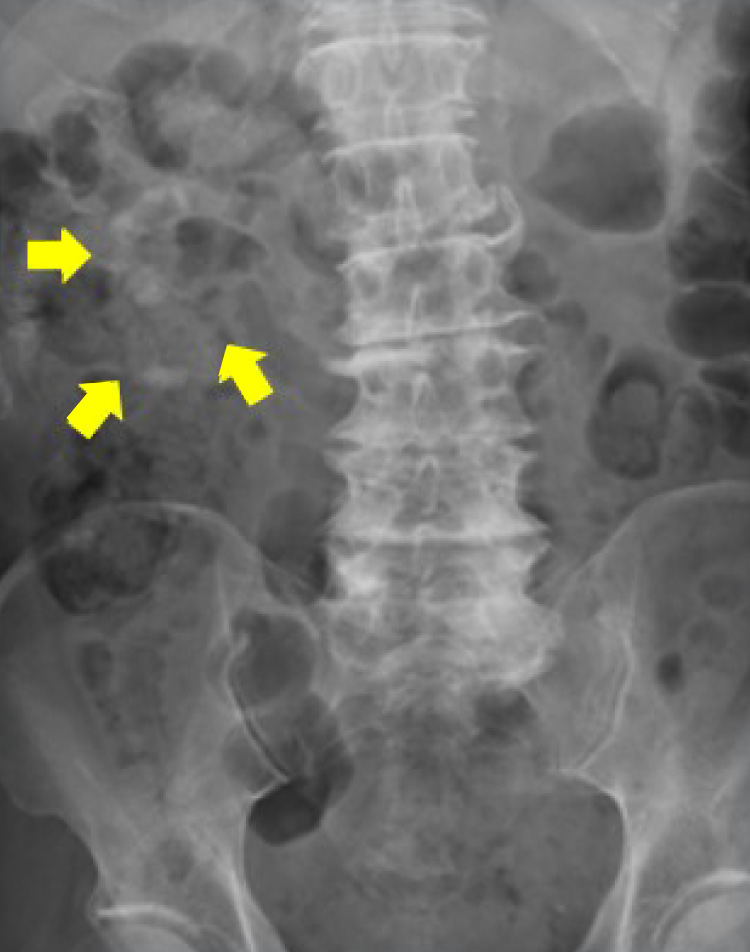

右完全サンゴ状結石

ECIRS後